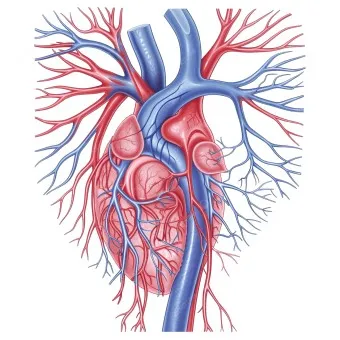

1. 심장 관련 원인

- 부정맥: 정상 심박수 범위 60-100회/분 이탈

- 심장 판막 이상: 증상 발현 시 심박수 변동 20% 이상

- 빈맥증: 휴식 시에도 심박수 100회/분 이상

- 서맥증: 심박수 60회/분 이하로 저하